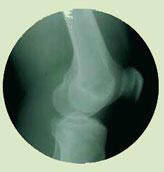

Des données observationnelles et expérimentales suggèrent qu'une faible consommation de vitamine K pourrait être associée à une augmentation du risque de fractures. Une méta analyse a passé en revue les essais randomisés contrôlés dans lesquels des adultes ont reçu des suppléments de phytonadione et de ménaquinone pendant plus de six mois. 13 essais ont été identifiés avec des données concernant la perte osseuse et 7 des fractures.

Toutes les études sauf une ont montré un intérêt de la phytonadione et de la ménaquinone dans la réduction de la perte osseuse. Les sept études faisant état d'effets sur les fractures étaient japonaises et ont utilisé de la ménaquinone.

Six de ces études ont utilisé une supplémentation quotidienne avec 45 mg de ménaquinone-4 et la 7e, 15 mg. 5 études portaient sur des femmes âgées et deux sur des hommes et des femmes.

La supplémentation en ménaquinone a eu pour résultat une diminution de 70 % des fractures de la hanche, de 60 % des fractures vertébrales et de 81 % de toutes les fractures non vertébrales.

Cette revue systématique suggère qu'une supplémentation avec de la phytonadione et de la ménaquinone-4 réduit la perte minérale osseuse. Il y a également un solide effet sur l'incidence des fractures parmi les patients japonais.